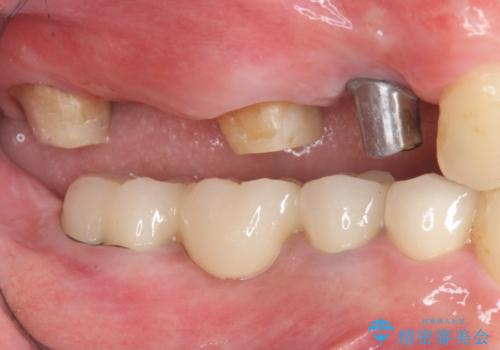

- 「少しずつ色々な箇所が悪くなり、歯医者に通い続けている。全ての歯を長持ちするような状態にできるような治療を受けたい。」、と全顎・総合的な治療を希望され来院されました。

根管治療・矯正治療・歯周外科・セラミック補綴を含む様々な治療オプションを駆使し、長期間良好な状態に保てるような治療計画を立案します。

矯正治療を絡めた総合的な治療をお行なったことで、理想的な咬合関係を確立し安定した噛み合わせで仕上げることができました。

また歯周外科を行うことで歯ぐきの腫れを改善し、清掃性を高めています。